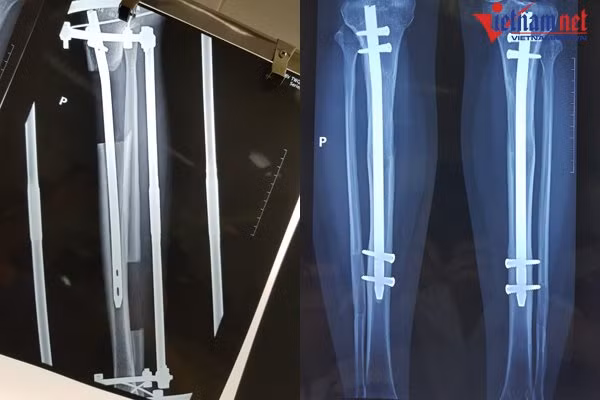

| Một chiếc đinh dài được đặt trong lòng ống tủy (trái) và bác sĩ sẽ bắt chốt 2 đầu đinh lại sau khi đạt chiều cao mong muốn |

Khi đạt đến chiều cao mong muốn, bác sĩ sẽ bắt chốt 2 đinh lại với nhau và tháo bỏ khung ngoài. Bệnh nhân sẽ được bó bột, sau đó bắt đầu tập đi dưới sự trợ giúp của khung hoặc nạng.